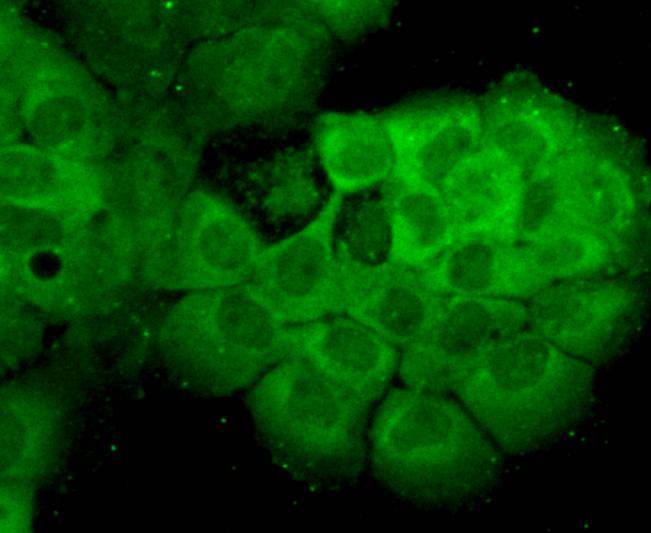

ICC staining HSP70 in SHG-44 cells (green). Cells were fixed in paraformaldehyde, permeabilised with 0.25% Triton X100/PBS.

ICC staining HSP70 in A431 cells (green). Cells were fixed in paraformaldehyde, permeabilised with 0.25% Triton X100/PBS.

ICC staining HSP70 in SKBR-3 cells (green). Cells were fixed in paraformaldehyde, permeabilised with 0.25% Triton X100/PBS.